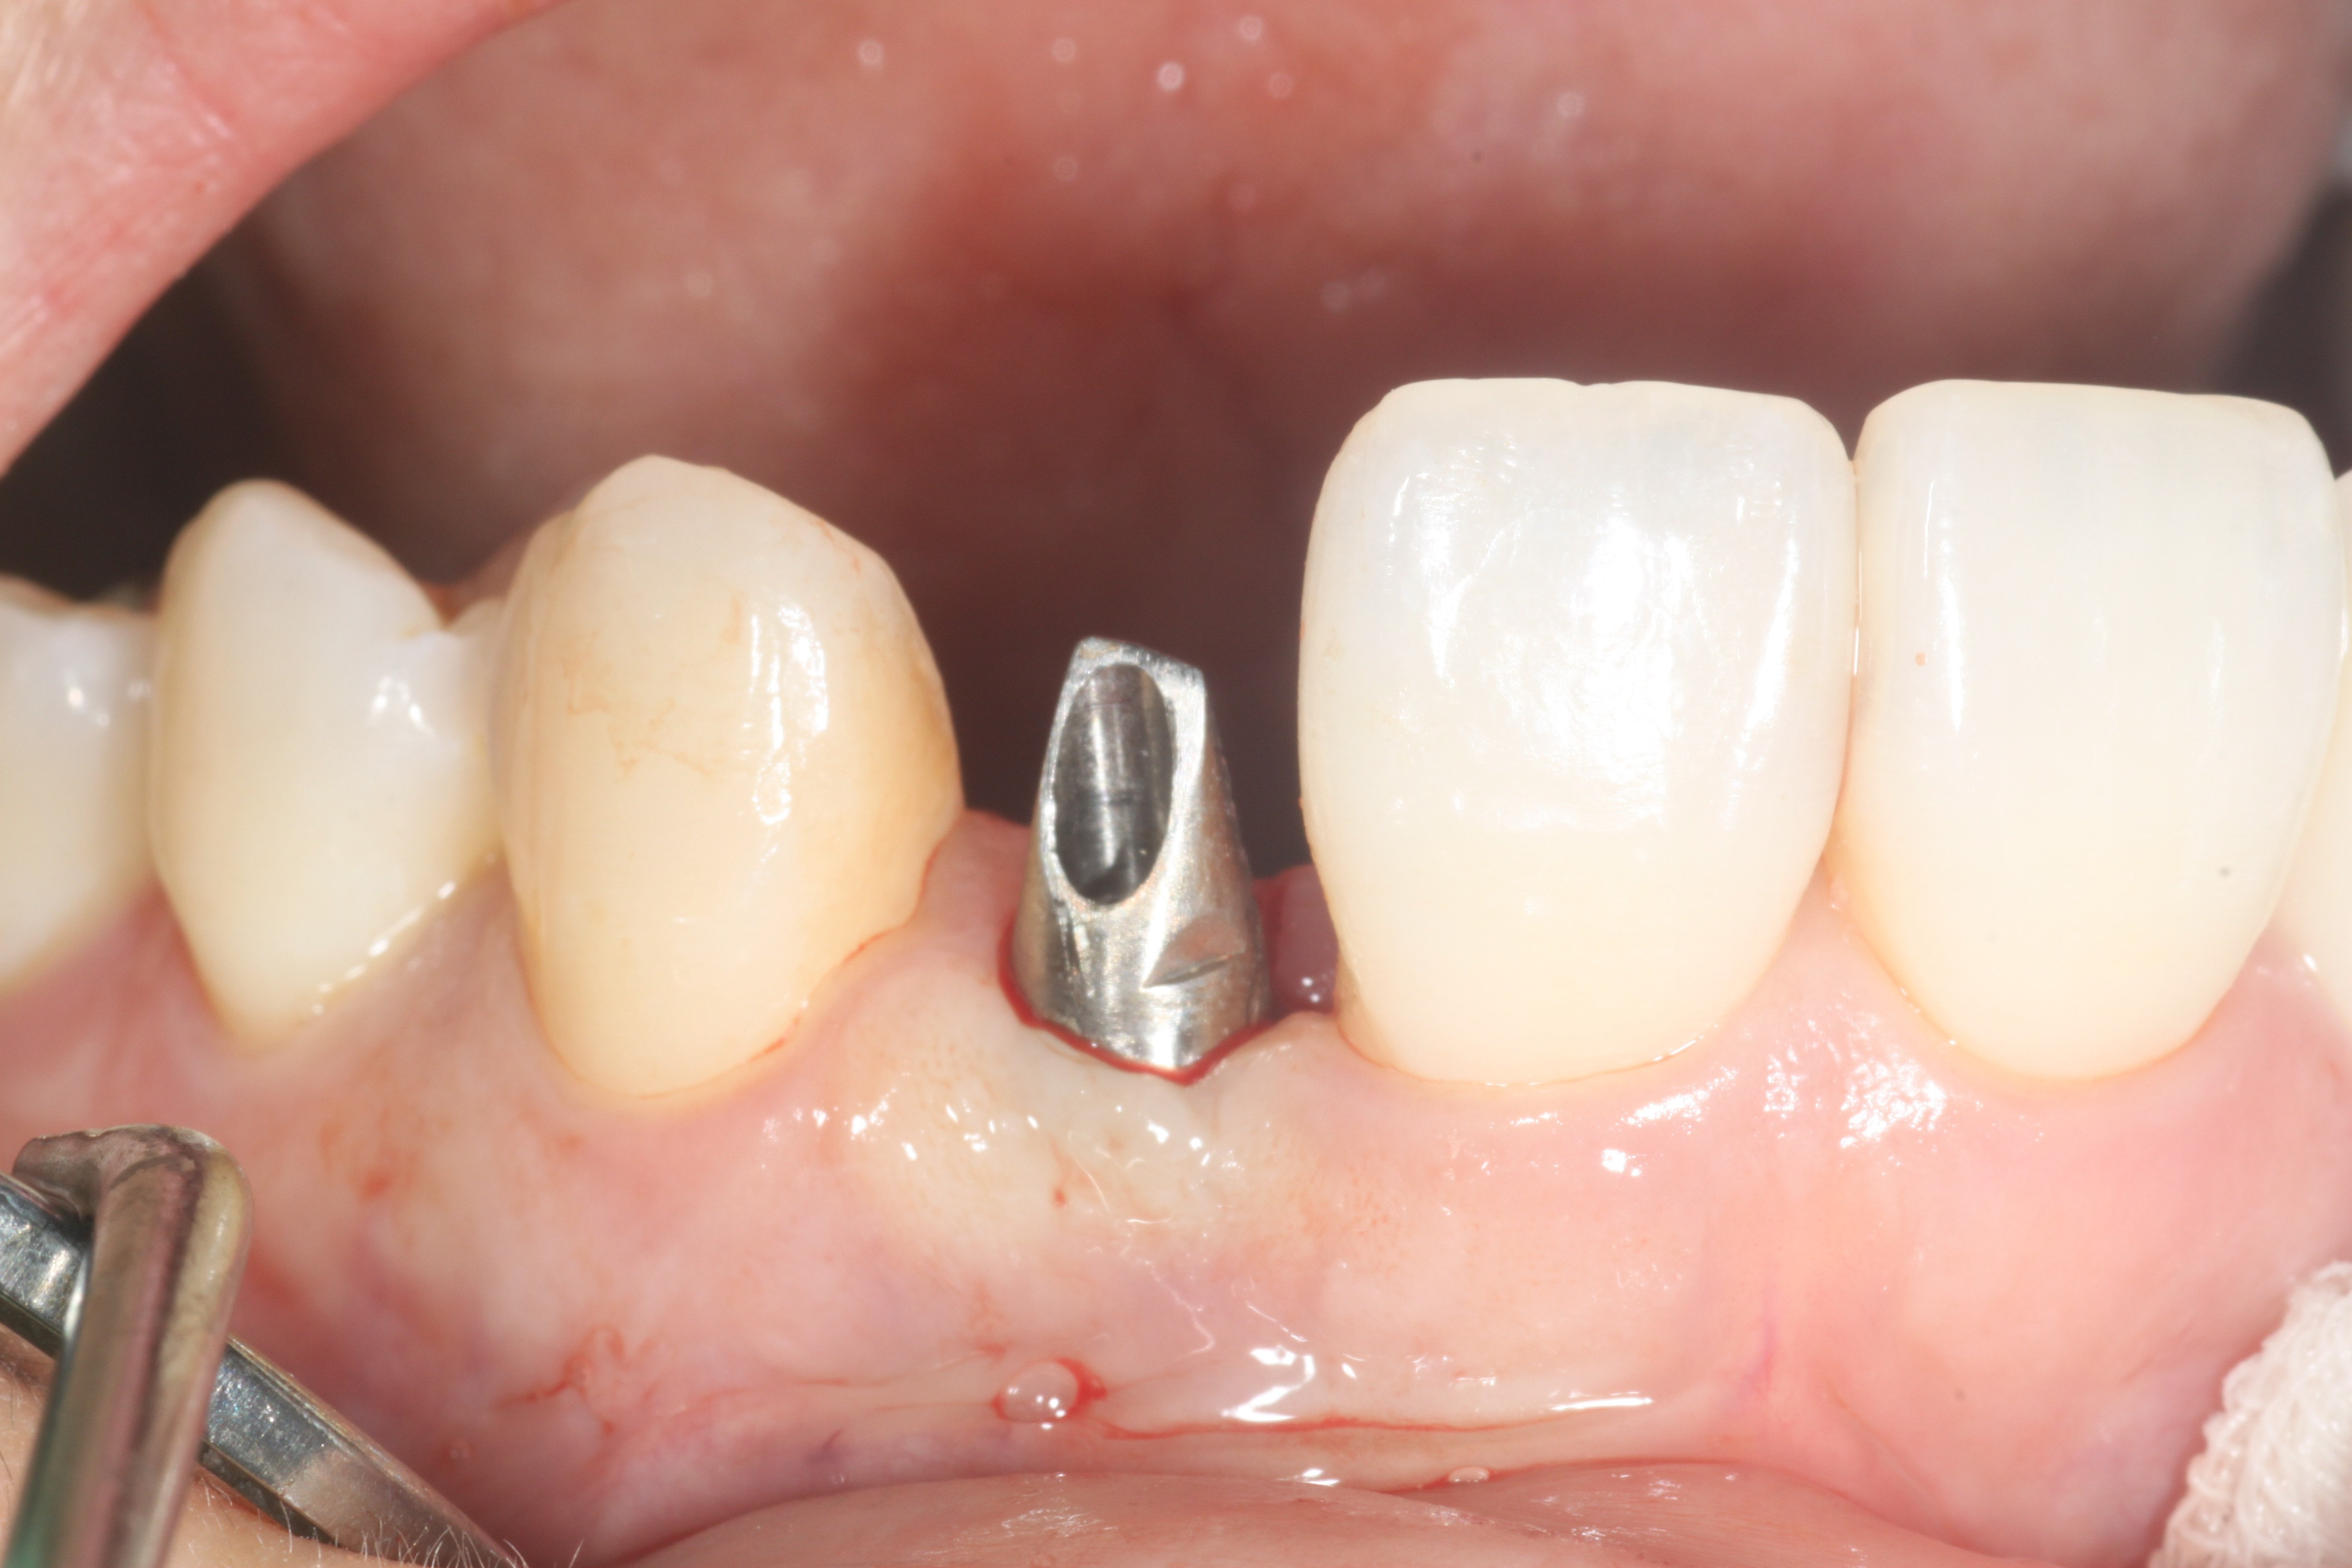

24³â 03 15ÀÏ ÀüÄ¡ºÎ½Ä¸³°í°ú °¡ÀÇÄ¡¸¦ ¸¸µé¾îÁÖ¾úÀ¾´Ï´Ù.

36¼¼¿© ȯÀÚºÐÀÔ´Ï´Ù.1¿ù¿¡ ¸¹ÀÌ Èçµé¸®°í »ÀÀÇ Èí¼ö°¡ ½ÉÇØ °ñÀ̽ĸ¸ ÇØ ³õ°í ÀÕ¸ö°ú °ñÁ¶Á÷À̾î´ÀÁ¤µµ Çü¼ºµÇ¾î ÀÓÇÁ¶õÆ®¸¦ ½Ä¸³ÇÏ¿´À¾´Ï´Ù.